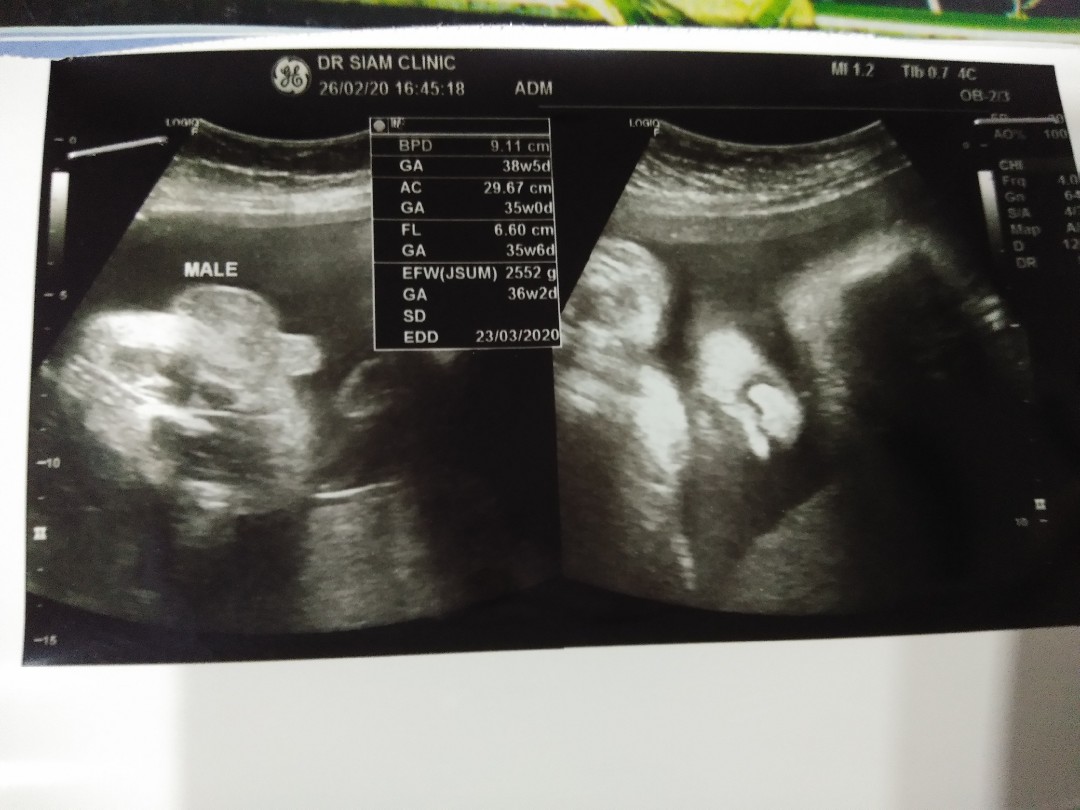

หมอบอกผู้ชายค่ะ

ดอกจำปีเลยค่ะ

หมอบอก ผช. ค่ะ

ชัดเจนค่ะ😁